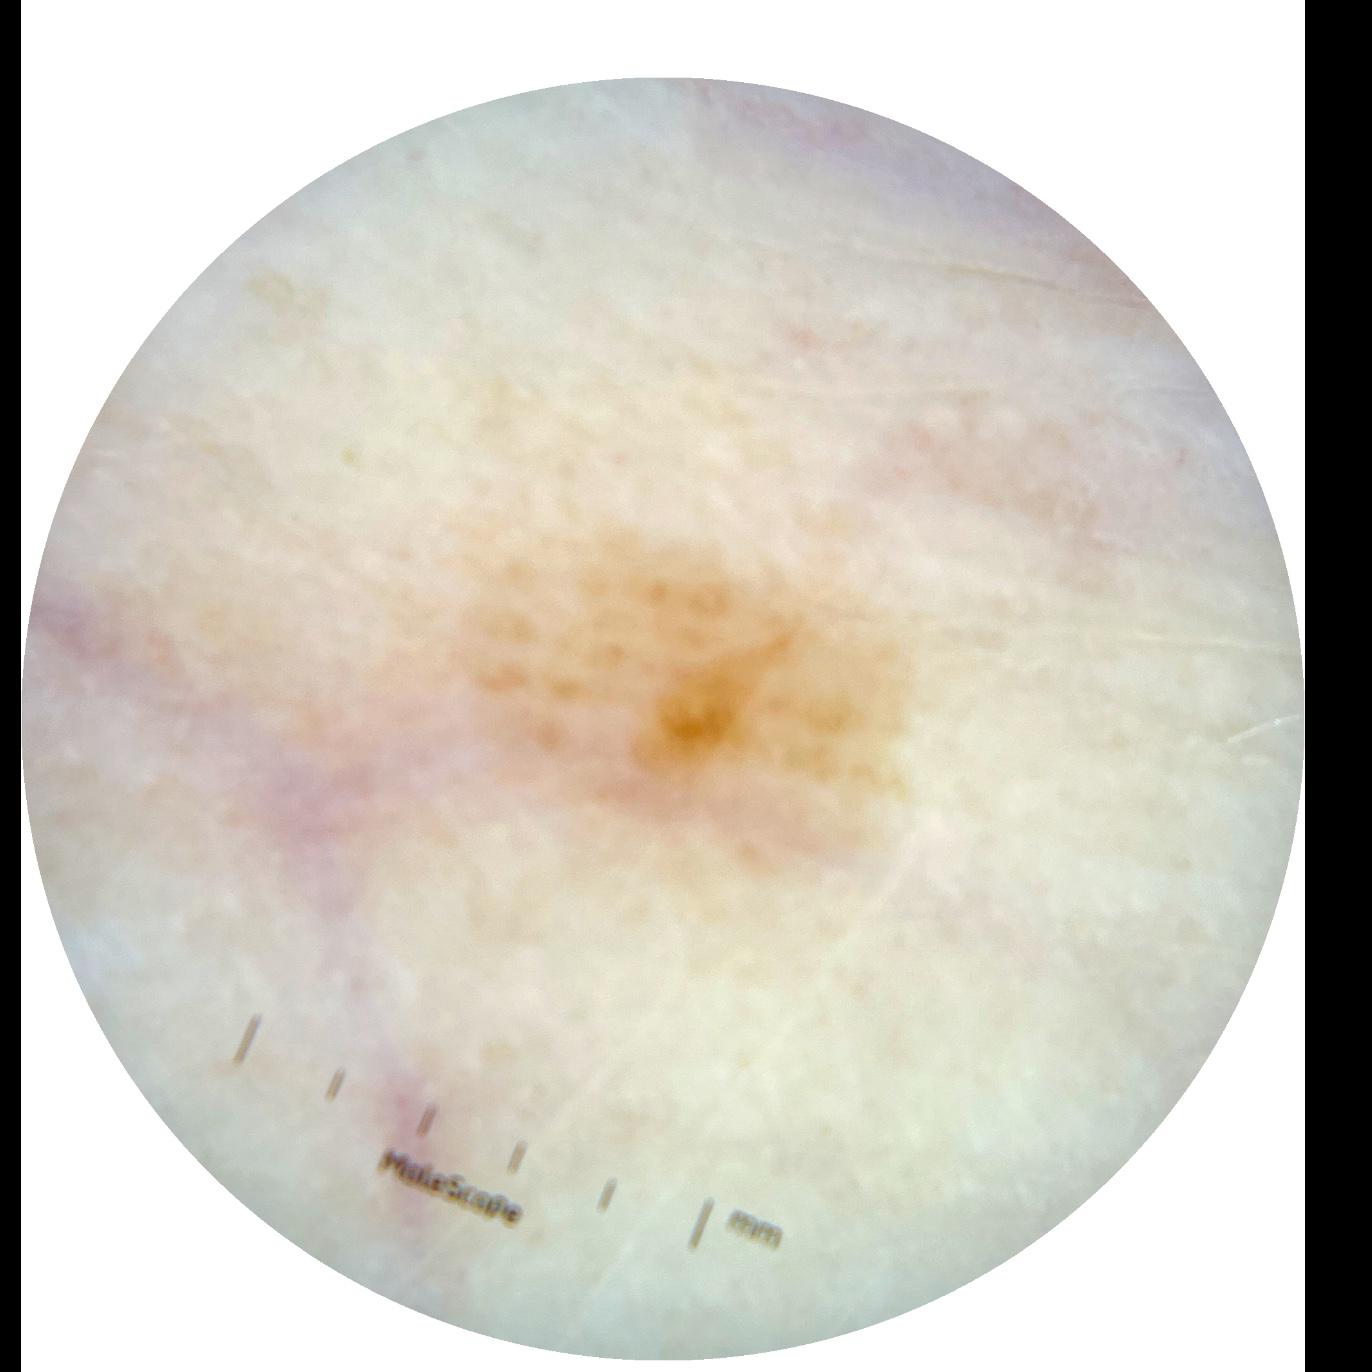

ISIC_0301375

anatom_site_1 Trunk

anatom_site_2 Anterior trunk

anatom_site_general anterior torso

diagnosis_1 Benign

image_type dermoscopic